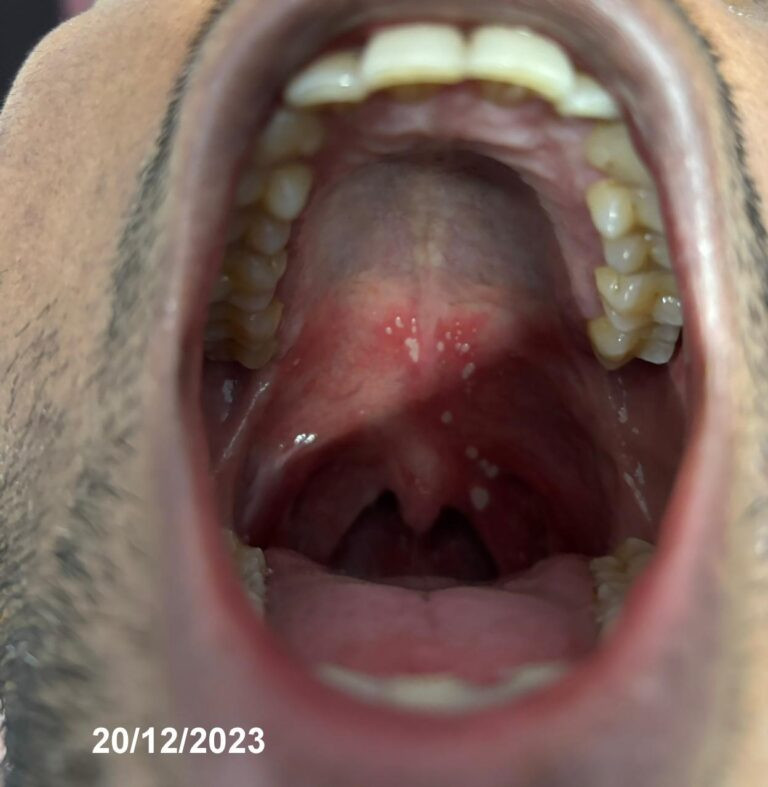

Case of mouth ulcer solved in just 4 days with the Cellular Detox Solution!